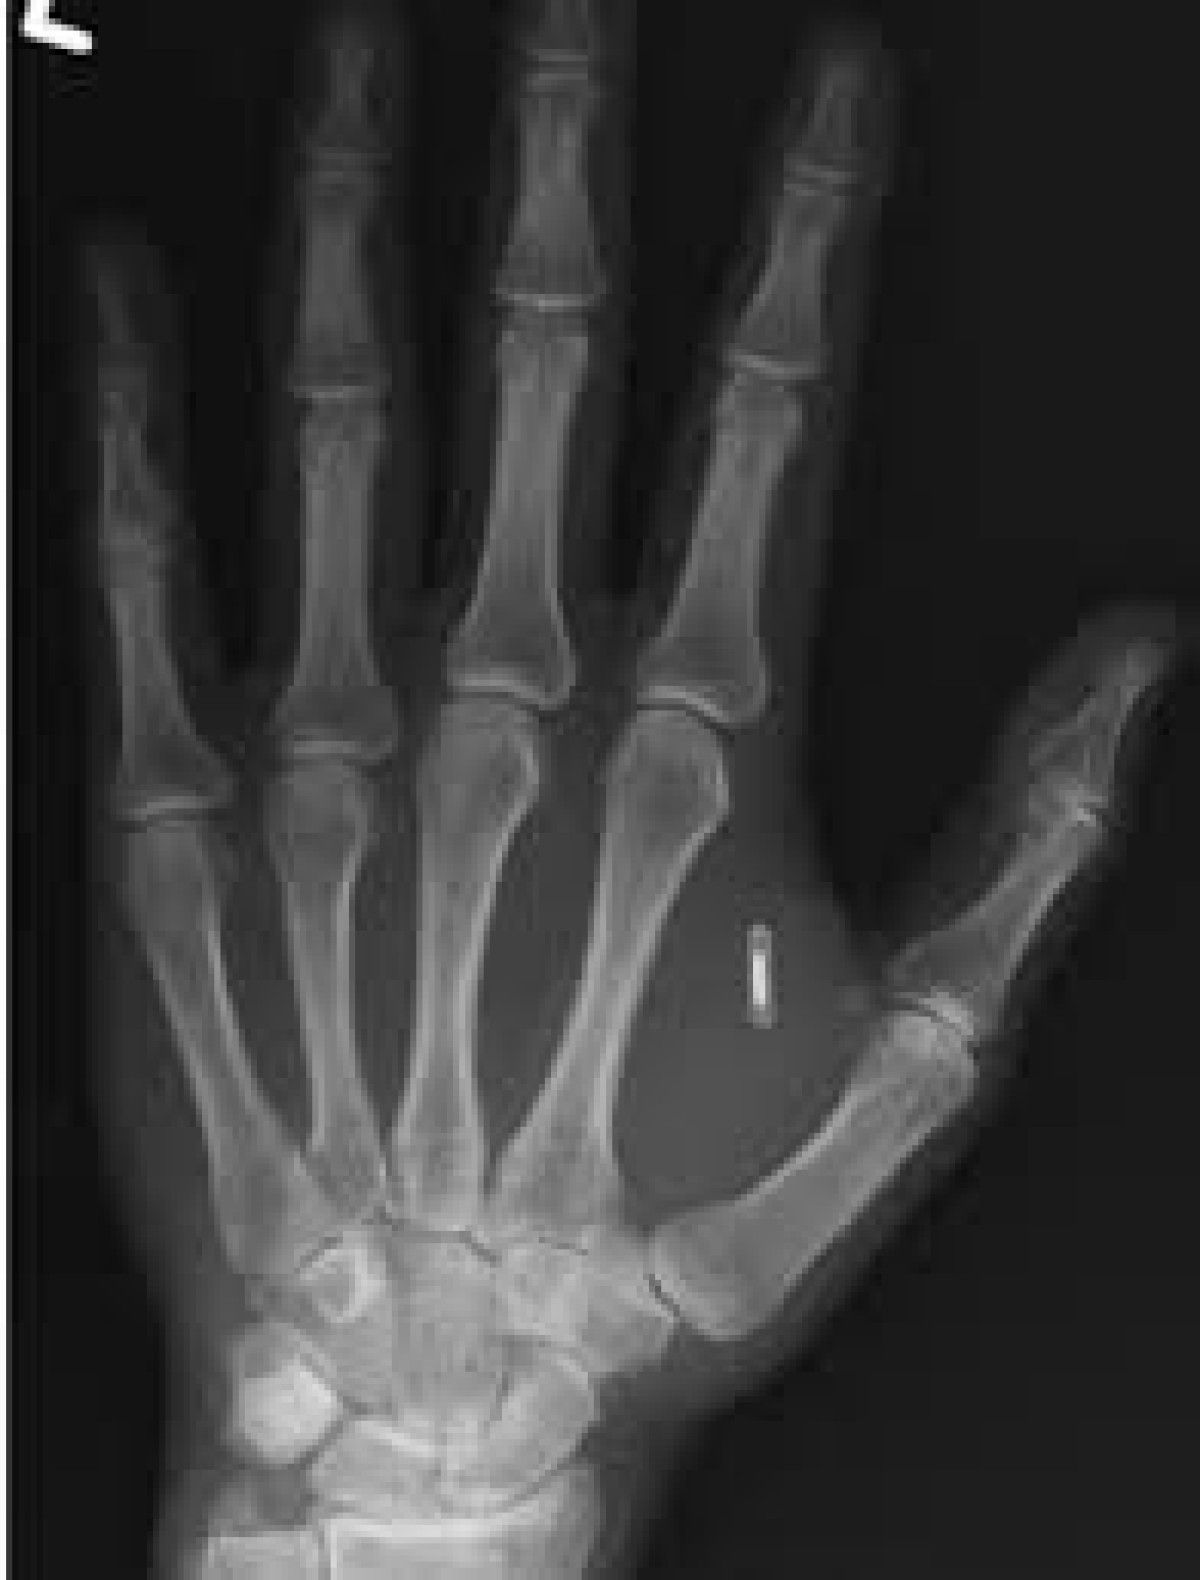

Paylaşılan röntgen görüntüsünde, Wang’ın başparmağı ile işaret parmağı arasındaki ete gömülü mikroçip net bir şekilde görülüyor. Biyolog durumu, “Şu an kendi siberpunk distopya hayatımı yaşıyorum, vücudumdaki teknolojiye erişimim kilitlenmiş durumda ve suç tamamen bende” sözleriyle özetledi.